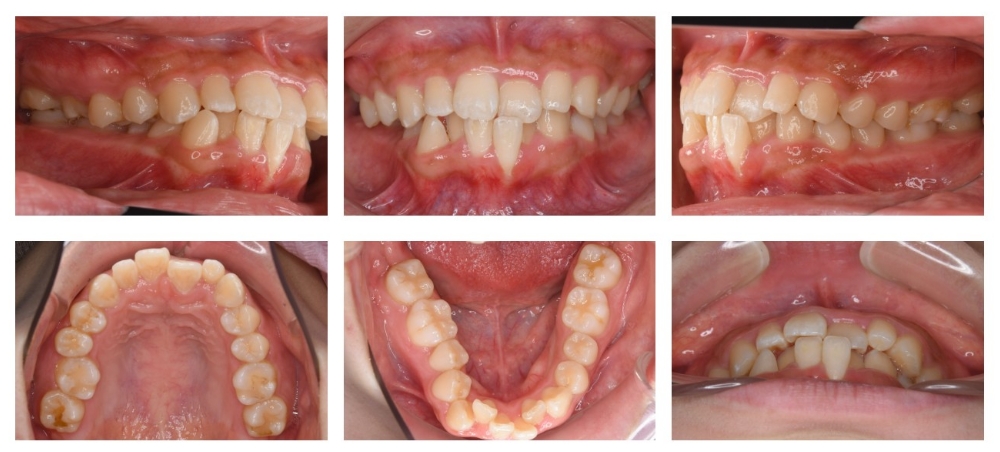

治療後

叢生 交叉咬合(Cross bite) 前歯 シザースバイト

主訴 横顔(口元が出ている), 笑った時の歯茎の見え方

年齢/性別 10代 / 女性

抜歯部位 非抜歯

使用装置 アライナー(インビザライン)

治療期間 5年4ヶ月

リテーナー 上LBR, 下LBR, 上クリアリテーナー, 下クリアリテーナー